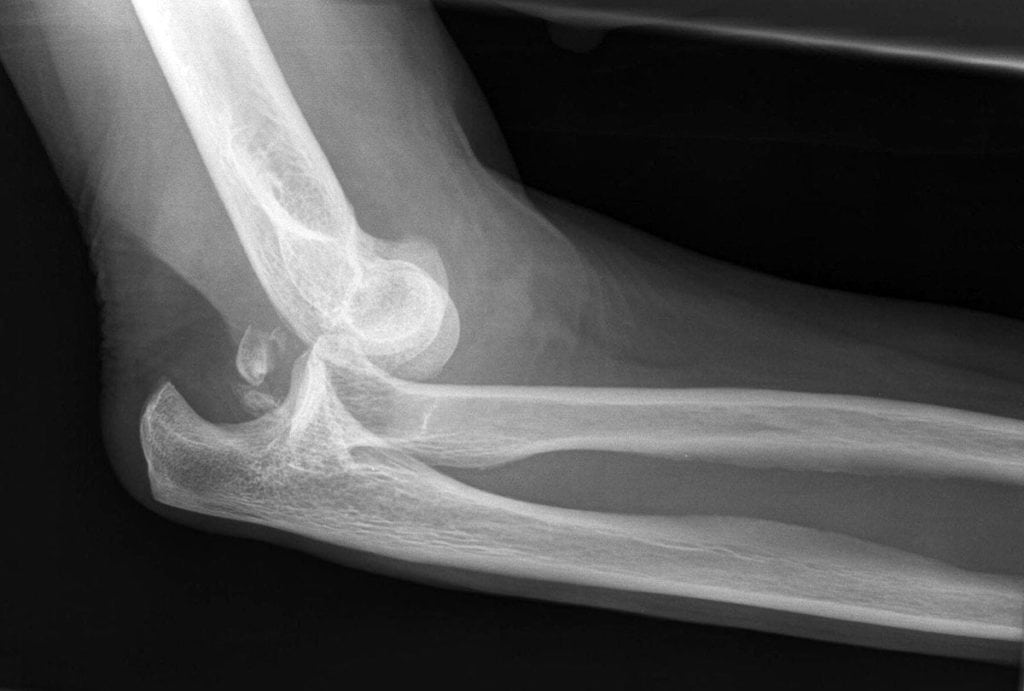

Для диагностики врачам обычно хватает клинических симптомов, осмотра пациента. С целью подтверждения диагноза больному делают рентгенографию локтевого сустава в двух проекциях. Исследование позволяет визуализировать смещение, выявить сопутствующие переломы. Рентгенографию выполняют до вправления и после него.

При диагностике вывихов важными внешними ориентирами служат локтевой отросток и надмыщелки плечевой кости. Когда рука разогнута, все они располагаются на одной прямой, образуя линию Гютера. При сгибании локтя под прямым углом они образуют равносторонний треугольник Гютера. При смещении эти три точки располагаются неправильно, асимметрично.